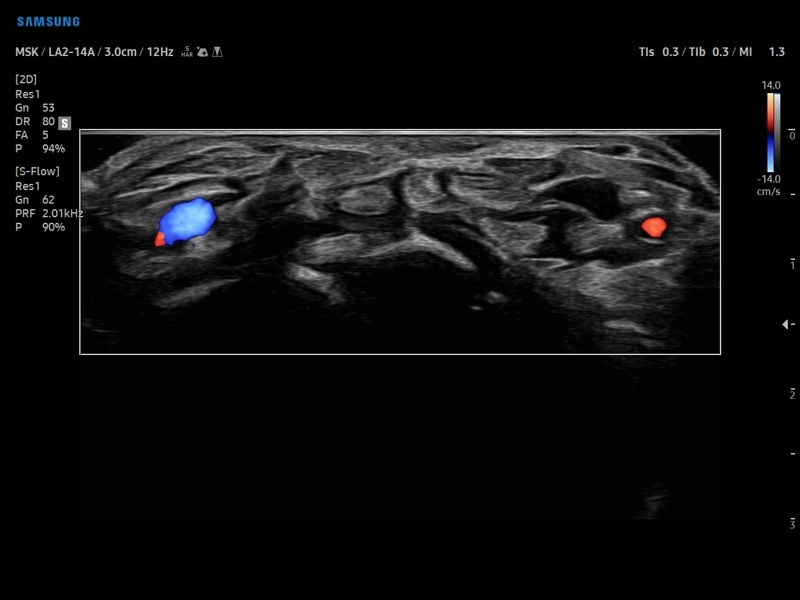

• Диагностика костно-мышечной системы

• Модуль NerveTrack – автоматическое определение срединного нерва в поперечном сечении с использованием искуственного интеллекта.